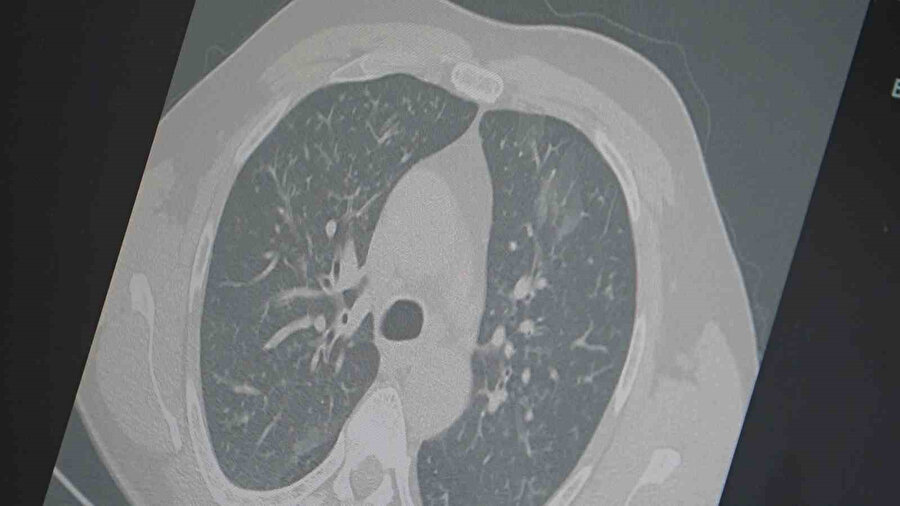

Dr. Özkaya, grip ve kovid 19’un zatürreye dönüşme riski taşıdığını vurgulayarak, "Grip veya kovid sonrası birçok hastamızda hastalık akciğerlere iniyor ve zatürre olarak karşımıza çıkıyor. Hastaneye yatan hasta sayısında da artış gözlemliyoruz" şeklinde konuştu.

"En ufak grip benzeri şikayeti olan vatandaşlarımızın evlerinde dinlenmelerini öneriyoruz. Uzamış öksürük ve nefes darlığı yaşayanların ise mutlaka doktora başvurarak akciğer röntgeni çektirmeleri ve uygun tedaviyi almaları gerekiyor."